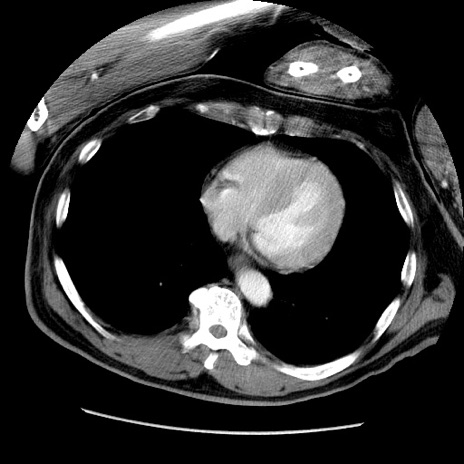

症例22(横断像)

【症例】50歳代男性

【主訴】腹痛

【現病歴】AVMからの被殻出血のため回復期リハ病棟入院中。 本日午後3時頃急に下腹部痛が出現した。

【既往歴】AVM、被殻出血、虫垂炎、高血圧

【身体所見】意識晴明、左半身不全麻痺、会話の理解は良好、36.5°C、腹部:膨隆、全体に板状硬、下腹部正中に圧痛点あり、反跳痛-、筋性防御不明、右下腹部にope scar

【データ】WBC 9400、CRP 0.06